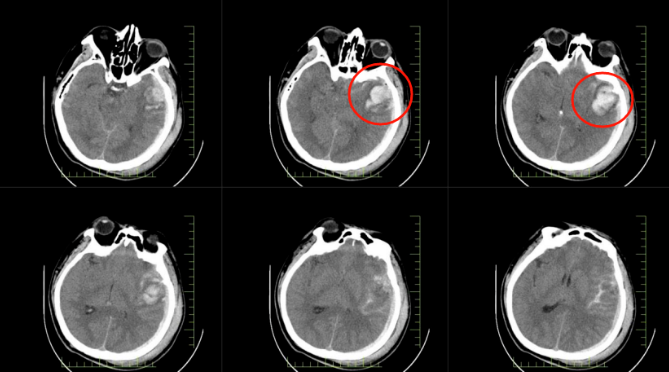

患者郭先生因高處墜落,送達(dá)醫(yī)院時(shí)已陷入昏迷。經(jīng)急診全面檢查,被確診為顱腦損傷重型、腦挫裂傷伴腦內(nèi)血腫、創(chuàng)傷性蛛網(wǎng)膜下腔出血等多項(xiàng)嚴(yán)重病癥。顱內(nèi)出血、顱壓驟升,每一項(xiàng)診斷都如同高懸的達(dá)摩克利斯之劍,威脅著患者的生命。

*患者顱內(nèi)出血影像圖

面對(duì)如此緊急的情況,患者身邊卻無(wú)直系親屬陪同。秉持 “生命至上” 的理念,長(zhǎng)春國(guó)文醫(yī)院迅速啟動(dòng)應(yīng)急預(yù)案。院領(lǐng)導(dǎo)果斷決策,第一時(shí)間開(kāi)通急救綠色通道,為患者的搶救爭(zhēng)取了寶貴的時(shí)間。與此同時(shí),神經(jīng)外科、手術(shù)室、麻醉科、重癥醫(yī)學(xué)科等多學(xué)科團(tuán)隊(duì)緊急集結(jié)。短短 30 分鐘,便完成了術(shù)前的各項(xiàng)準(zhǔn)備工作,患者被快速推進(jìn)手術(shù)室。